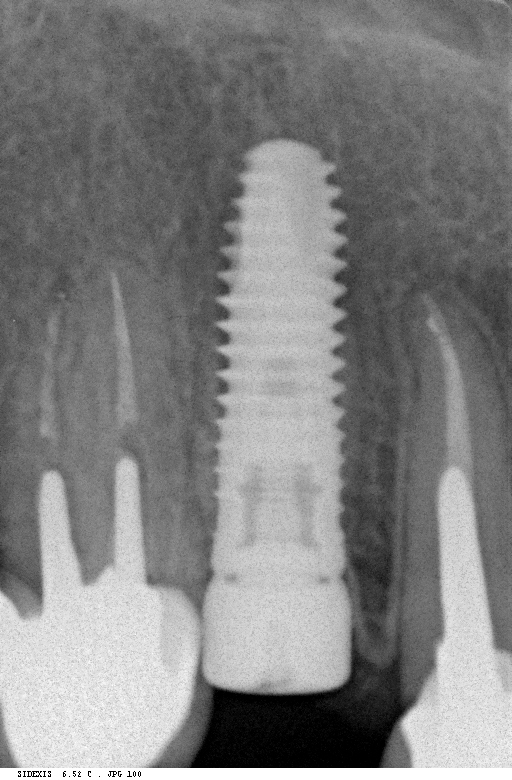

Рентген имплантов Alpha Bio: диагностика и качество